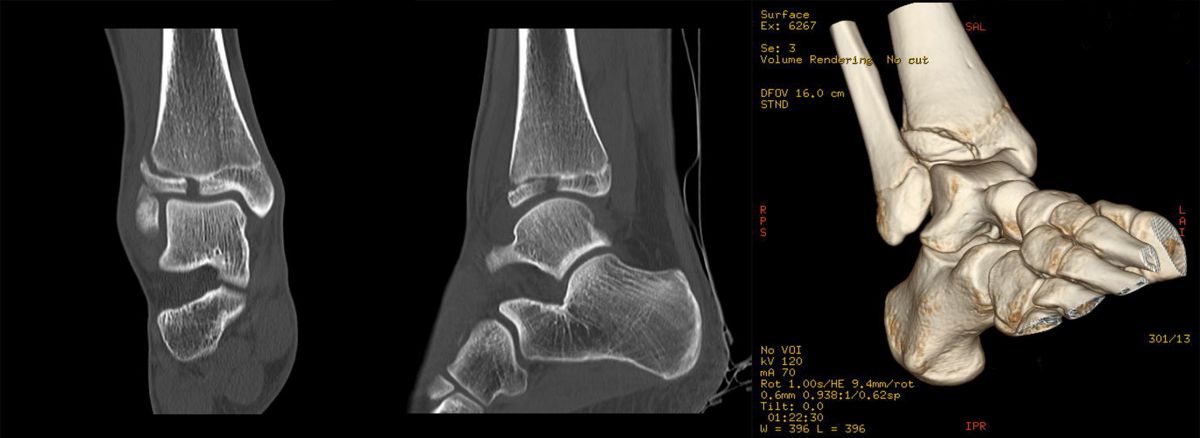

Computertomografie

Die Computertomografie liefert die höchste Auflösung für knöcherne Verletzungen und die Untersuchung dauert nur wenige Sekunden. Nachteilig ist die hohe Strahlenbelastung, die bei einem Vielfachen von konventionellen Röntgenbildern liegt. Bei komplexen Gelenksfrakturen hat die Computertomografie aber auch beim Kind ihre Berechtigung und erleichtert die Planung der Rekonstruktion.

Der teilweise komplexe Frakturverlauf bei Übergangsfrakturen lässt sich im CT zuverlässig darstellen 10. Der erfahrene Untersucher kann bereits mit Röntgenaufnahmen des Sprunggelenks in zwei Ebenen in Verbindung mit zwei 45° Schrägaufnahmen sehr umfassende Aussagen zum Frakturverlauf treffen (v. Laer 2013), die Präzision und Aussagekraft der Computertomografie ist aber zweifelsohne überlegen und wird von den meisten Behandlern bevorzugt 11, auch wenn sich zu diesem Thema in der Literatur eine teilweise sehr emotional geführte Diskussion findet. Einigkeit hinsichtlich der Indikation für ein Schnittbildverfahren besteht bei Triplane-Frakturen, wenn Zweifel darüber bestehen, inwieweit die metaphysäre Fraktur den tragenden Gelenkanteil tangiert 12.